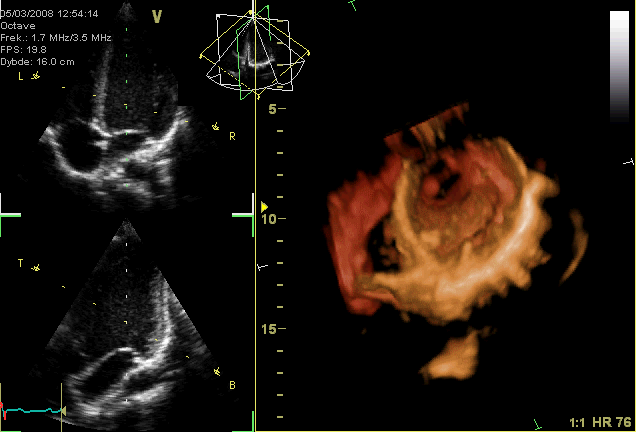

This image presents a sophisticated look at cardiac imaging, combining 2D echocardiogram views with a 3D reconstruction of the heart. Such advanced diagnostic tools are vital for non-invasively assessing heart structure and function, providing critical insights into cardiac health and disease. Understanding how to interpret these images is fundamental for cardiologists in diagnosing a wide range of cardiovascular conditions.

V Octave: This likely refers to the imaging modality or software used, indicating an advanced echocardiography system. “Octave” may signify its capability for detailed, high-resolution imaging.

Frek.: 1.7 MHZ/3.5 MHZ: This indicates the transducer frequency used for the ultrasound examination. Lower frequencies (e.g., 1.7 MHz) typically penetrate deeper, while higher frequencies (e.g., 3.5 MHz) offer better resolution for superficial structures.

FPS: 19.8: Stands for Frames Per Second, indicating the rate at which the ultrasound images are captured and displayed. A higher FPS allows for better visualization of rapid cardiac motion.

Dybde: 16.0 cm: This refers to the depth setting of the ultrasound scan, indicating that the machine is imaging structures up to 16.0 centimeters from the transducer. This parameter is adjusted based on the patient’s anatomy and the structures being examined.

HR 76: This is the heart rate, measured at 76 beats per minute. A normal heart rate is a key indicator of cardiac rhythm and overall cardiovascular health.

2D Echocardiogram Views (Upper and Middle Panels): These grayscale images represent standard two-dimensional ultrasound cross-sections of the heart. They allow for real-time visualization of cardiac chambers, valves, and wall motion, showing the heart’s pumping action.

3D Reconstruction (Right Panel and Lower Left Panel): This vividly colored image showcases a three-dimensional model of the heart, constructed from multiple 2D ultrasound slices. It provides a comprehensive spatial understanding of the heart’s external and internal structures, including the great vessels and chambers.

The combination of 2D and 3D echocardiography provides a holistic view of cardiac health. The 2D views offer dynamic, cross-sectional insights into myocardial contractility, valve motion, and the presence of any abnormal fluid collections around the heart. The 3D reconstruction, on the other hand, allows for a comprehensive spatial understanding of complex cardiac anatomy, which is particularly useful for assessing congenital heart defects or guiding complex procedures. For example, assessing the heart rate (HR 76 bpm in this image) alongside visual data gives a complete picture of cardiac performance.